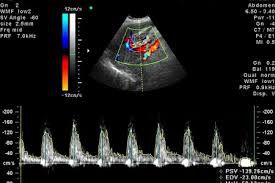

Доплер вимірює як звукові хвилі відбиваються від рухомих об'єктів. Комп'ютер обробляє інформацію і створює двомірне кольорове зображення, що показує, чи є труднощі в кровотоці, наприклад, через відкладення холестерину - атеросклеротичних бляшок.

Сучасні апарати з постійно-хвильовим, імпульсно-хвильовим і кольоровим доплером об'єднують інформацію, що отримується при всіх цих видах досліджень. В В-режимі можна побачити структуру судинної стінки. Доплер показує, як тече кров по судинах вимірює швидкість потоку крові. УЗДГ також може бути корисно для установки діаметра посудини, а також величини стенозу (закупорки) кровоносної судини.

Традиційне УЗД використовує безболісні звукові хвилі, нечутні людським вухом, які відбиваються від судин. Ультразвукове дуплексне може використовувати зображення, які закодовані кольором для того, щоб показати доктору, де кровотік сильно блокований, а також швидкість і напрямок потоку крові. Ваш лікар може рекомендувати Доплер, щоб полегшити діагностику або досліджувати стану, які впливають на судини. Ці стани включають: